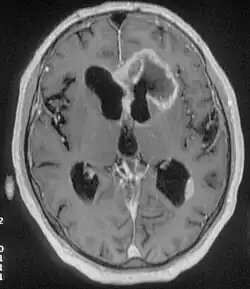

There are many different causes of frontal lobe epilepsy ranging from genetics to head trauma that result in lesions in the frontal lobes.[4] Although frontal lobe epilepsy is often misdiagnosed, tests such as prolonged EEG monitoring, video EEG and/or an MRI scan of the frontal lobes can be administered in order to reveal the presence of a tumor or vascular malformation.[4] Unlike most epileptic EEGs, the abnormalities in FLE EEGs precede the physical onset of the seizure and aid in localization of the seizure's origin.[4] Medications such as anti-epileptic drugs can typically control the onset of seizures, however, if medications are ineffective the patient may undergo surgery to have focal areas of the frontal lobe removed.[4]

Neuroimaging for diagnosis